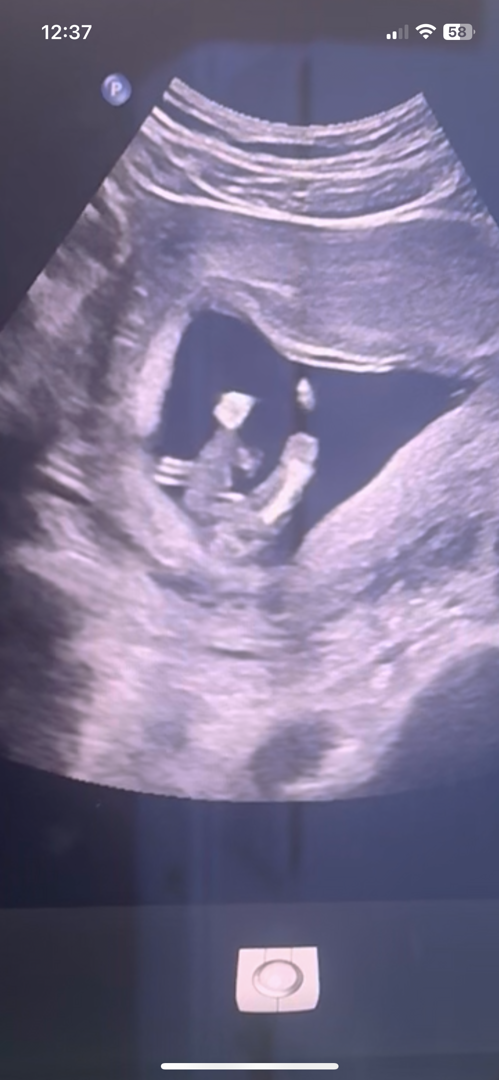

14주 1일차 성별알려주세요

14주인데 다리사이에 없는거 보면 딸이겠죠??

딸이네요 !ㅎㅎㅎ

딸같아요!